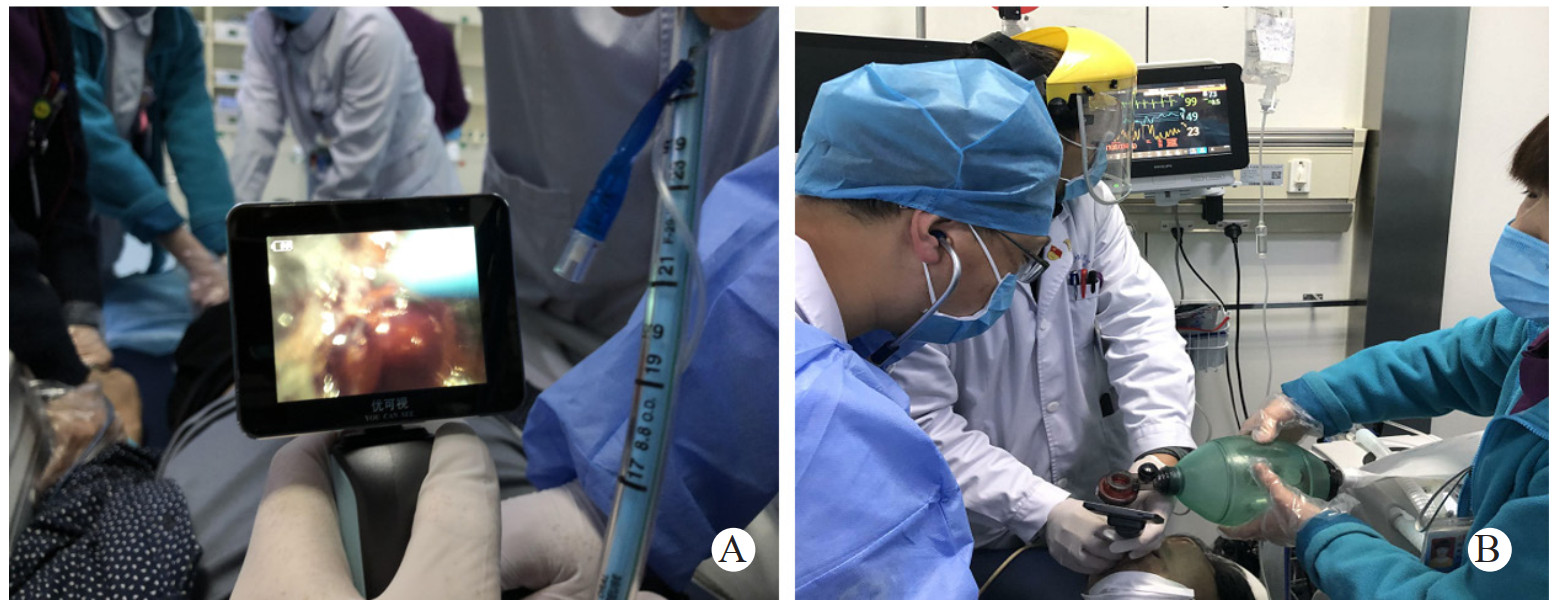

急诊观察室留观约5 min患者突然出现高度吸气性呼吸困难,三凹征明显,口唇发绀,烦躁不安,起身用手抠抓颈部,心电监测显示SpO2快速进行性下降,最低达20%左右,心率亦伴随SpO2下降进行性下降,2 min左右患者意识丧失、呼吸停止。立即予以心肺复苏,尝试用人工气囊辅助通气,但人工气囊通气失败,患者气道梗阻即使人工气囊安全阀关闭下加压仍无法有效通气。视频喉镜打开口咽部观察发现会厌高度充血肿胀呈球型,喉腔黏膜充血肿胀明显,会厌肿胀压迫喉口,声带未窥及,喉黏液较多,披裂及声门均看不见,考虑为急性会厌炎合并Ⅳ度喉梗阻。紧急采用视频喉镜联合Bougie气管插管(图 3),为减少导管对水肿会厌及气道的损伤选择选内径6.0的气管导管套于Bougie,经视频喉镜明视下以Bougie沿会厌与咽后壁之间缝隙成功插入声门,在Bougie引导下送入气管导管,导管置入深度23 cm,听诊双肺呼吸音清晰对称,未闻及明显干湿啰音,固定气管导管后连接呼吸机SIMV模式,参数设定潮气量6 mL/kg,呼吸频率15次/min,给氧浓度100%。监测显示SpO2由测不出逐渐上升至99%左右。约5 min后患者自主呼吸恢复,20 min左右意识逐渐恢复,生命体征平稳,复查颈部及胸部CT气管导管在位(图 4)。入院后行常规气管切开术,继续抗生素、糖皮质激素等药物治疗,4 d后检查见会厌肿胀消退,无呼吸困难,复查X线及颈部CT提示会厌水肿明显消退(图 5),9 d后拔管,10 d后康复出院,随访半年未出现任何并发症。

| A为视频喉镜直视Bougie引导下气管插管; B为插管后患者脉氧逐渐上升 图 3 采用视频喉镜联合Bougie气管插管 |

急性会厌炎采用视频喉镜联合Bougie引导下经口气管插管很好的避免了上述这些问题。该操作简便、快速,急诊科医师本身掌握气管插管技术,经过短期培训则可完全掌握气管插管技术。首先视频喉镜可以提供良好的声门视野,操作全过程均在可视下操作,解剖位置清晰,视频喉镜与Bougie联合应用可以解决声门暴露良好却不能置人导管的问题,从而降低插管难度、提高一次性插管成功率,缩短插管时间[18-19]。其次Bougie直径较气管导管明显减小,前端圆钝,因此插入声门时产生的阻力减少,更容易通过狭小的开口,Bougie前端进入声门后即可借助于Bougie的引导下顺势置入气管导管,同时减少会厌及周围组织损伤。患者拔管后发音正常,电子喉镜检查会厌及声带未见任何损伤。再次该方法对于特殊体位,如侧卧位、半坐位的气管插管尤为方便。会厌炎患者不需要患者平躺,为经口插管提供了良好的体位,也保留一定的自主反射,为患者可能发生的“零通气”争取了时间,为相对平稳而安全的方法。此方法可在最短的时间内重建呼吸通道,为下一步治疗赢得了时间。